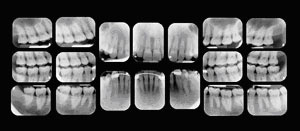

Your first visit to the doctor typically includes an x-ray that allows the doctor to view the structure of the jaw, the position of any teeth that have not yet erupted, malformed roots, and tooth decay.

x-rays